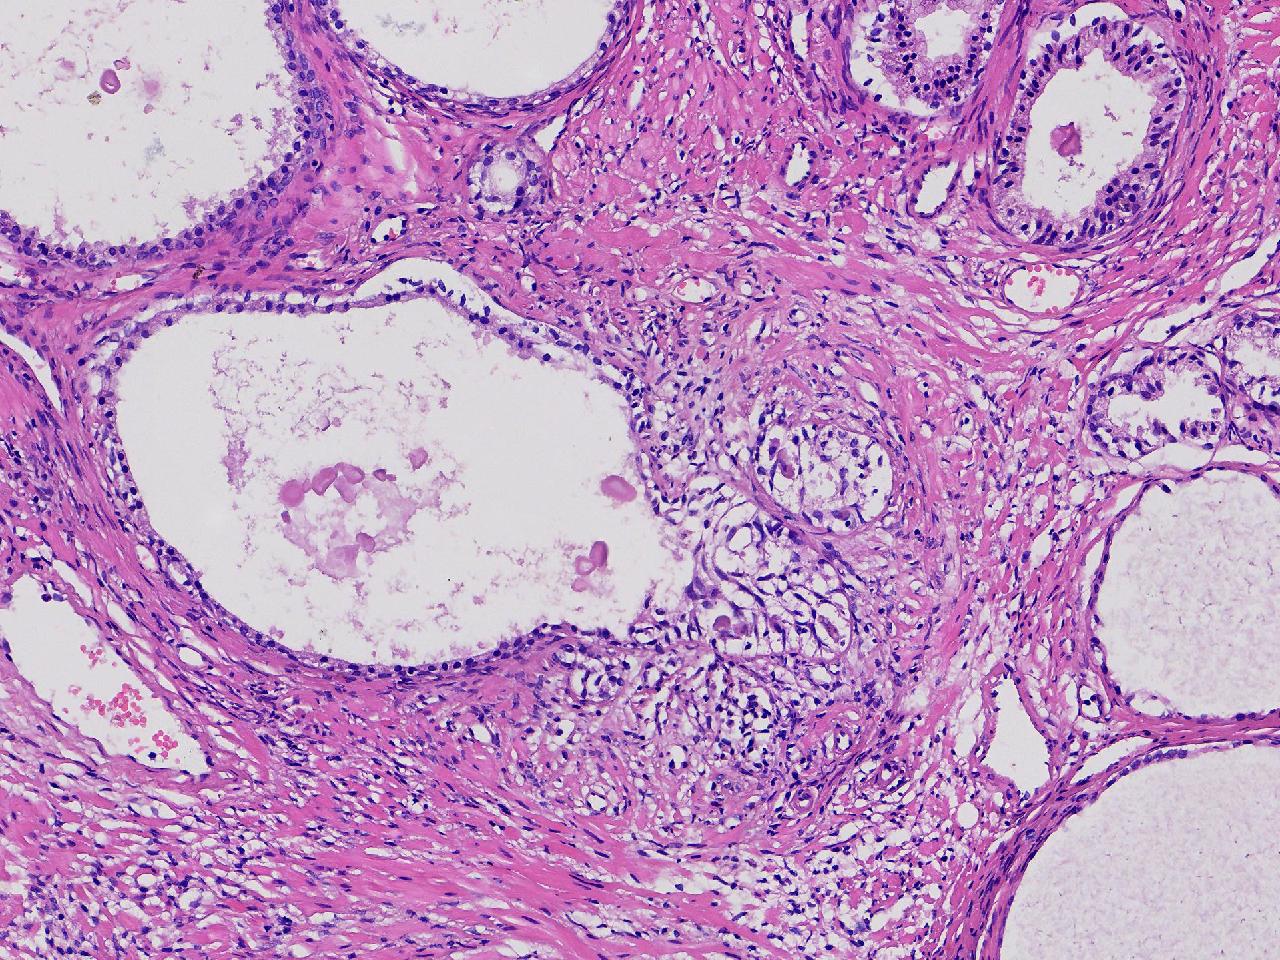

良性前列腺增生吧?

性别

男

年龄

65岁

临床诊断

前列腺电切组织

一般病史

进行性排尿困难半年余。

标本名称

前列腺

大体所见

图3

、良性前列腺增生

BPH.